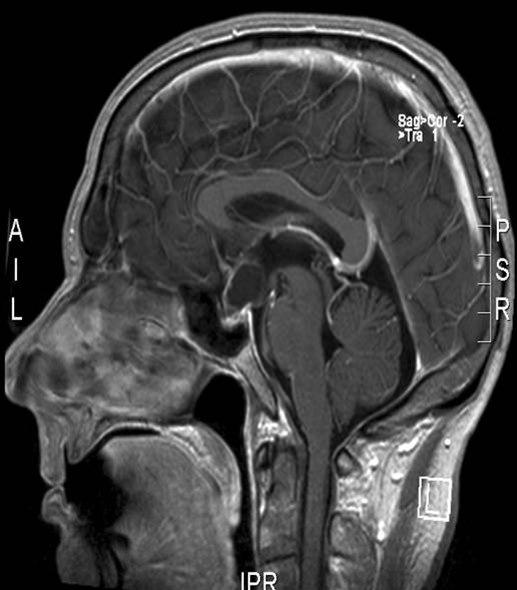

Kraniopharyngeom, sagittalt snitt

kraniopharyngeom 1

Gjengitt med tillatelse av Radiologisk avdeling, Universitetssykehuset Nord-Norge